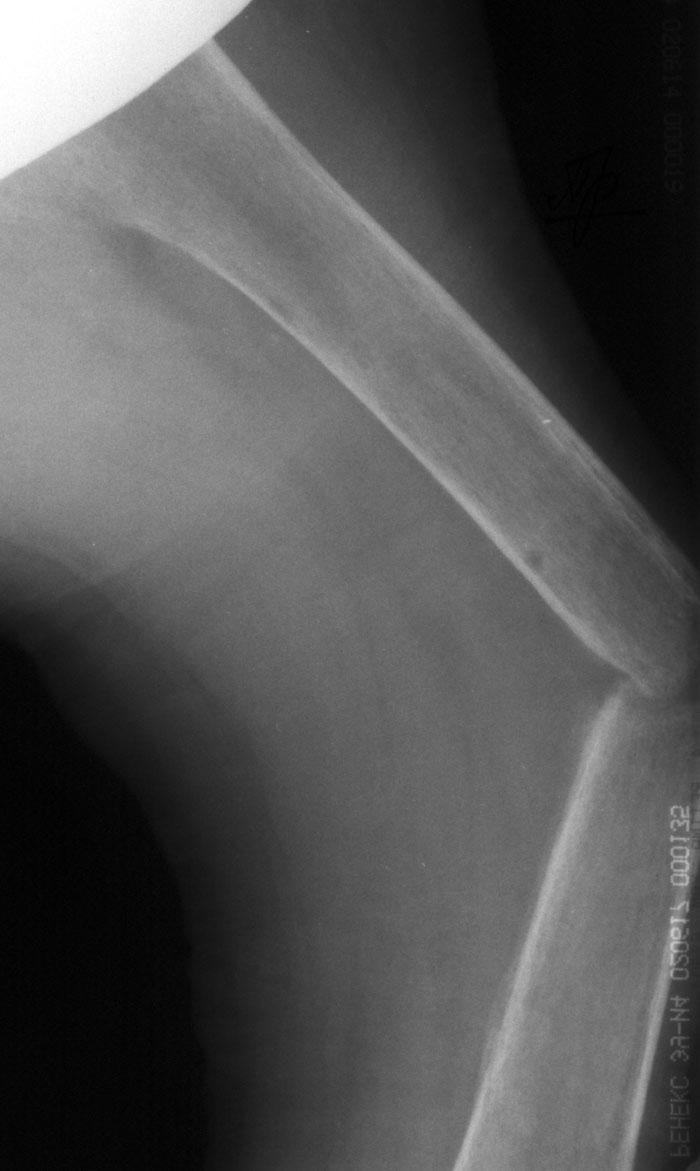

Выписка из амбулаторной карты пациента, 1980 г.р.Находится под наблюдением в поликлинике КНЦ РАН. Состоит на "Д" учёте по заболеваниям:Ювенильный идиопатический генерализованный остеопороз. Деформация грудной клетки за счёт множественных переломов грудины, рёбер. S-образный кифосколиоз грудного отдела позвоночника.Синдром гипофосфатемии неясного генеза. ВСД по кардиальному типу.Инвалид 1-й группы с детства. Последние 4 года не может передвигаться, возникают патологические переломы. Живёт в семье, материально-бытовые условия удовлетворительные.За последние 2 года состояние значительно ухудшилось - усилилась общая слабость, участились патологические переломы, которые не срастаются. Постоянно лежит в постели. Постоянный приём препаратов кальция и диеты с повышенным содержанием кальция, фосфора и белка эффекта не дают. С 11.07.2002 по 30.07.2002 г. лечился в травматологическом отделении АЦГБ с переломом костей правого предплечья со смещением. С 24.08.2002 по 08.09.2002 г. лечился в терапевтическом отделении по поводу острого бронхита с бронхоспастическим компонентом.На сегодняшний день статус. Состояние относительно удовлетворительное. В сознании. Положение вынужденное: сидя в инвалидном кресле, сам встать на ноги и передвигаться не может, туалет только с помощью родственников. Бледный, астеничный. Выраженная деформация грудной клетки, выраженный кифоз и сколиоз грудного отдела позвоночника. Экскурсия грудной клетки ограничена. Участие в акте дыхания вспомогательных межрёберных мышц. Пальпация грудной клетки безболезненна. Деформация всех крупных и мелких суставов за счёт увеличенных эпифизов. Деформация длинных трубчатых костей, мышцы рук и ног атрофичны. Температура - 36,8, ЧД - 29 в минуту. Дыхание жёсткое, проводится во все отделы. Слева от угла лопатки и в аксиллярной области влажные мелкопузырчатые хрипы, в межлопаточной области с обеих сторон свистящие хрипы. Пульс 90 ударов в минуту, ритмичный, симмитричный, слабого наполнения и напряжения. АД 120\80 мм рт. ст. Границы относительной сердечной тупости не расширены. Тоны сердца громкие, ритм правильный. Язык влажный, блестит. Живот при пальпации мягкий, не вздут, симметричный, участвует в акте дыхания, безболезненный. Печень по краю рёберной дуги. Стул регулярный, оформлен, без патологических примесей. Мочеиспускание свободное, безболезненное. Симптом Пастернацкого отрицателен с обеих сторон. Отёков нет.Анализ крови общий 26.08.2002: Hb-146 г\л, Эр.-4,8, ЦП-0,91, Лейк.-6,4, п.-4, с.-45, э.-5, м.-11, СОЭ-4 мм\ч.Анализ мочи общий 26.08.2002: Уд. вес-1025, белок-0,01, сахар-нет, лейк.-0-1 в поле зр., слизь+++, бактерии+.Анализ крови биохимический 26.08.2002: глюкоза-4,9, АЛТ-0,3, АСТ-0,5, биллирубин-11,9, креатинин-44,2, мочевина-3,8, СРБ (+).Анализ крови на микрореакцию - отрицательный.Флюрограмма за 2002: Резко выраженная деформация грудной клетки за счёт множественных переломов рёбер, грудины. Инфильтративных теней в лёгких не определяется. По сравнению с предыдущим исследованием от 01.12.2000 г. - ухудшение: нарастают деформация грудной клетки и позвоночника.ЭКГ за 2002 год: Синусовая тахикардия с ЧСС 88 в минуту. Отклонение ЭОС вправо. Признаки нарушения процессов реполяризации миокарда задней стенки левого желудочка. Повидимому, изменения ЭКГ обусловлены позиционными изменениями, возможно астеничным телосложением.Дополнительные методы исследования.Рентген правого предплечья (17.10.2002): Металлоостеосинтез по поводу перелома обеих костей правого предплечья в н\з: признаки репарации практически не определяются, сохраняется диастаз между отломками.Рентген правого предплечья (24.04.2003): Металлоостеосинтез по поводу перелома обеих костей правого предплечья в н\з: признаки репарации отсутствуют, формируются ложные суставы. Резко выраженный остеопороз.Рентген правого бедра (18.02.2003): Несросшийся перелом правого бедра на границе с\з и н\з со смещением отломков под углом открытым кнутри. Формирующийся ложный сустав. Выраженный остеопороз костей.Рентген правого бедра (24.04.2003): Угловое смещение отломков правого бедра увеличилось. Признаки репарации крайне вялые: по наружному краю отломков формируются замыкательные пластинки - ложный сустав. Выраженный остеопороз.